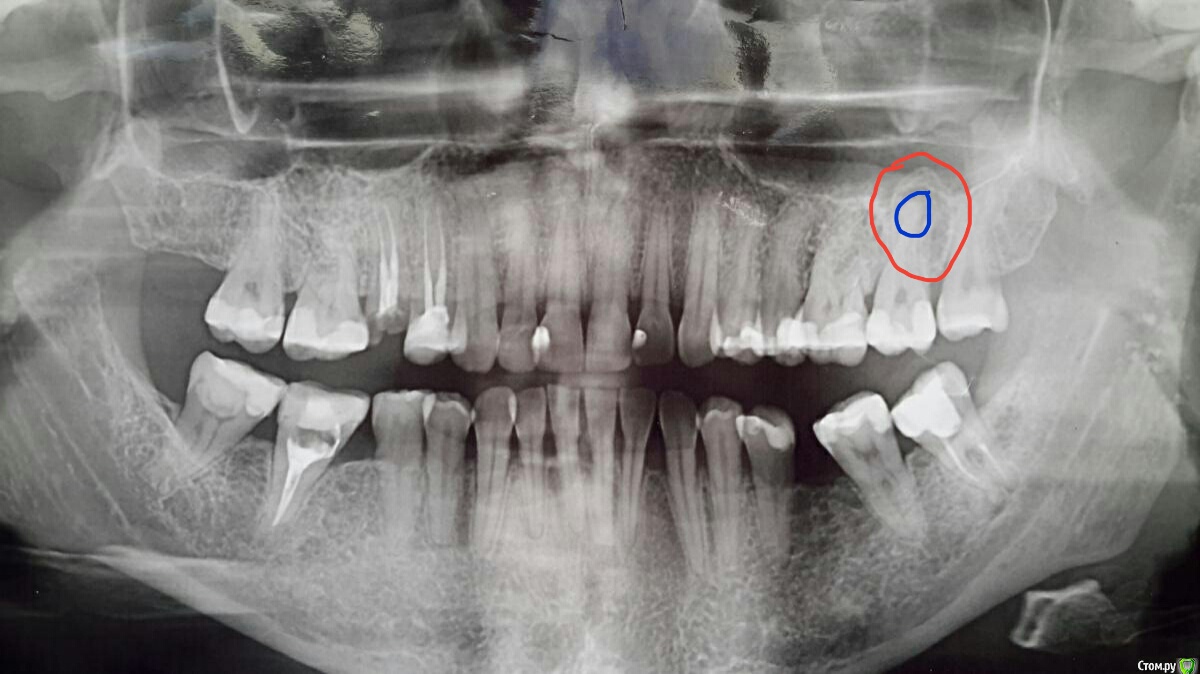

velena37 Опубликовано 15 марта, 2020 Автор Поделиться Опубликовано 15 марта, 2020 А можно еще вопрос? Киста это то, что синим или то, что красным? Ссылка на комментарий

red_butler Опубликовано 15 марта, 2020 Поделиться Опубликовано 15 марта, 2020 А можно еще вопрос? Киста это то, что синим или то, что красным?Синим, но это не киста а периодонтит Ссылка на комментарий

velena37 Опубликовано 15 марта, 2020 Автор Поделиться Опубликовано 15 марта, 2020 Синим, но это не киста а периодонтитПолучается в 38 зубе тоже периодонтит (там тоже мешочки какие-то)? Ссылка на комментарий

red_butler Опубликовано 15 марта, 2020 Поделиться Опубликовано 15 марта, 2020 Получается в 38 зубе тоже периодонтит (там тоже мешочки какие-то)?Ага Ссылка на комментарий